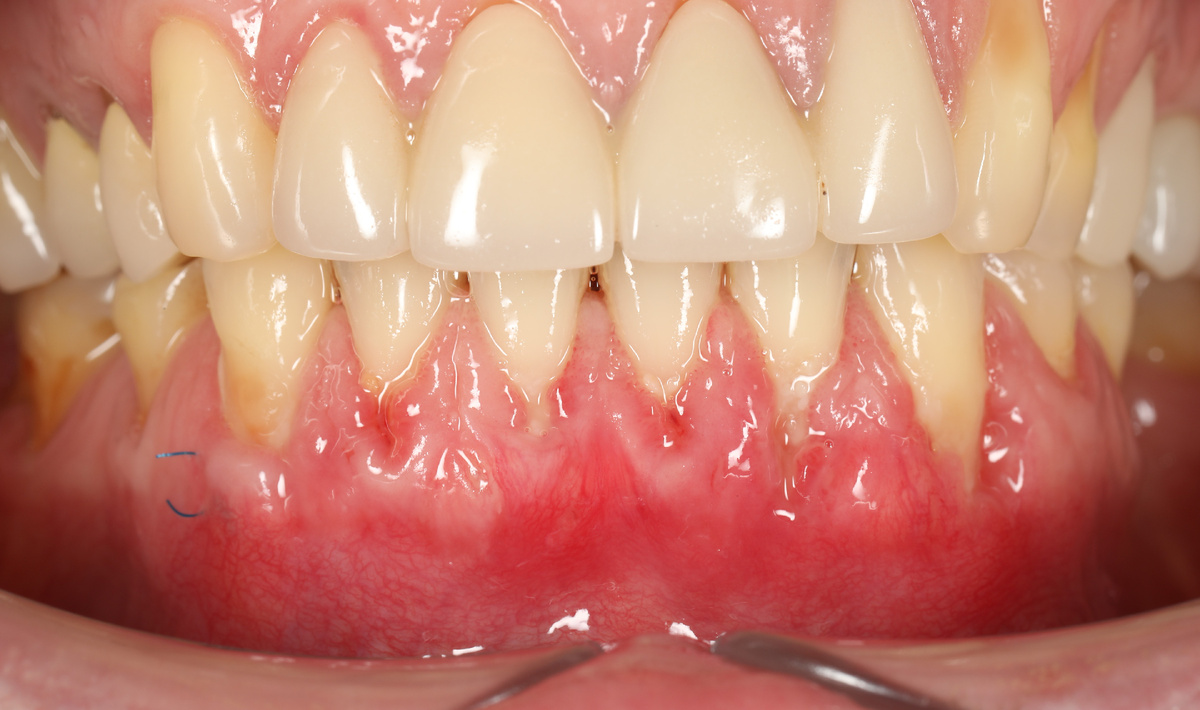

Сразу после снятия швов (через 10 дней после операции) рецессии выглядят вот так:

фото через 2 недели после операции. Полное заживление занимает месяц - два, за это время трансплантат успевает прижиться и сформировать новый уровень десны.

Как видим, десна уже выше, чем была и в основном закрывает корни зубов.

К сожалению, фотографию после окончательного формирования десны мы получить не смогли, так как пациентка приезжает к нам из другого города, однако, и на этом этапе результат уже виден.